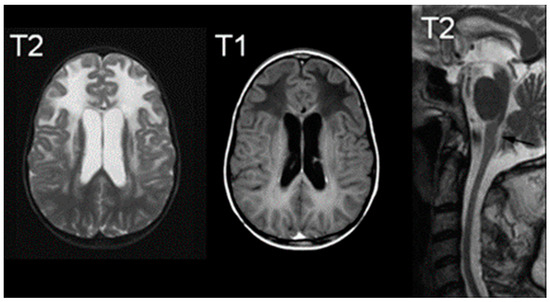

2.4. Pelizaeus–Merzbacher Disease